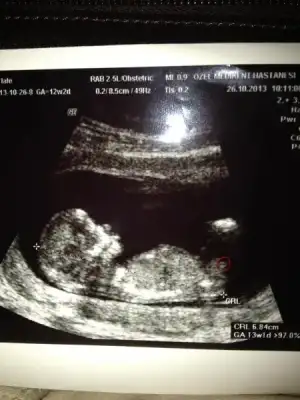

dr soylemeden siz gorun genital nub teorisi ( bebegin cinsiyeti)

Kimler kimler yazdı?herkesin 29 ekim bayramını kutlarım. benim fotoma da bakıp bir yorum yapabilir misiniz? 12 +2 de. sağdaki çıkıntı paralel gibi duruyor sanki. sizce o nub mu?

arkadaşlar sadece görebildiklerime yorum yapabiliyorum ama ben de tam bilmiyorum yani sadece tahmin ediyorum

bu bebiş erkek gibi eğer gördüğüm nubsa

Eki Görüntüle 843501 Eki Görüntüle 843502 Sanırım ben yüklerken biraz küçük yüklemişim şimdi en net 2 fotoyu seçerek tekrar yükledim. belirttiğim gibi bu resımde 11+4teyiz çok merak içindeyim lütfen yorum :)

nubu pararlel görünüyor erkeklerin dik oluyor eğer gördüğüm nubsa tabi canım

ama en iyi 13. haftada belli oluyor nuba göre

senin aslında doktor bilmesi gerekir bu haftanda

anladım doktor tam bişey soylemek istemedi artık ben çok kız istiyorum diyemi bilmiyorum ama bana erkek gibi geldi dedi sonraki aya çağırdı normal kontrole ama ben bu hafta başka bi doktora gidicem 16 haftalık dolu dolu inşallah kesin öğrenirim bu arada eğer o görünen nubsada çok uzun bi nub hayrlısı artık :)))

Eki Görüntüle 842353 resim buydu

bana erkek gibi geldi çok anladığımdan değil sadece gördüğüm nubsa eğer paralel değil baya dik hayrlısı olsun inşallah bu arada bende tam olarak öğrenemedim senin gibi araştırmadayım :)

bak doktor da erkek gibi demiş :) ama nubun da yanılma payı oluyor gönlünden ne geçiyorsa o olsun inşallahanladım doktor tam bişey soylemek istemedi artık ben çok kız istiyorum diyemi bilmiyorum ama bana erkek gibi geldi dedi sonraki aya çağırdı normal kontrole ama ben bu hafta başka bi doktora gidicem 16 haftalık dolu dolu inşallah kesin öğrenirim bu arada eğer o görünen nubsada çok uzun bi nub hayrlısı artık :)))

Teşekkür ederim cevapladıgin için. Ben anlayamadım da bacak engel olmuş nub görünümüne sanırım

Eki Görüntüle 843501

Eki Görüntüle 843502

Yokmu ßaşka yorumm Lütfenn :)

Merhabalar. Resimde işaret ettiğim şey nub mu sizce? Var mı tahmin yürütebilecek? Çok tşk

sanmiyorum onun altindaki olabilir erkek gibi

Eki Görüntüle 843501 Eki Görüntüle 843502 Yokmu ßaşka yorumm Lütfenn :)

görünmüyor görebildiklerime tahmin yapiyorum ben canim

Merhabalar. Resimde işaret ettiğim şey nub mu sizce? Var mı tahmin yürütebilecek? Çok tşk

o bacakları onun gerisindeki nub erkek gibi bebek

büyük ihtimal erkek gibi geldi bana

Canım sağol doğruymuş doktor erkek dedi :)) 14.haftada öğrendik ama anca yazabildim şimdi 18 hafta 3 günlük bebeğim